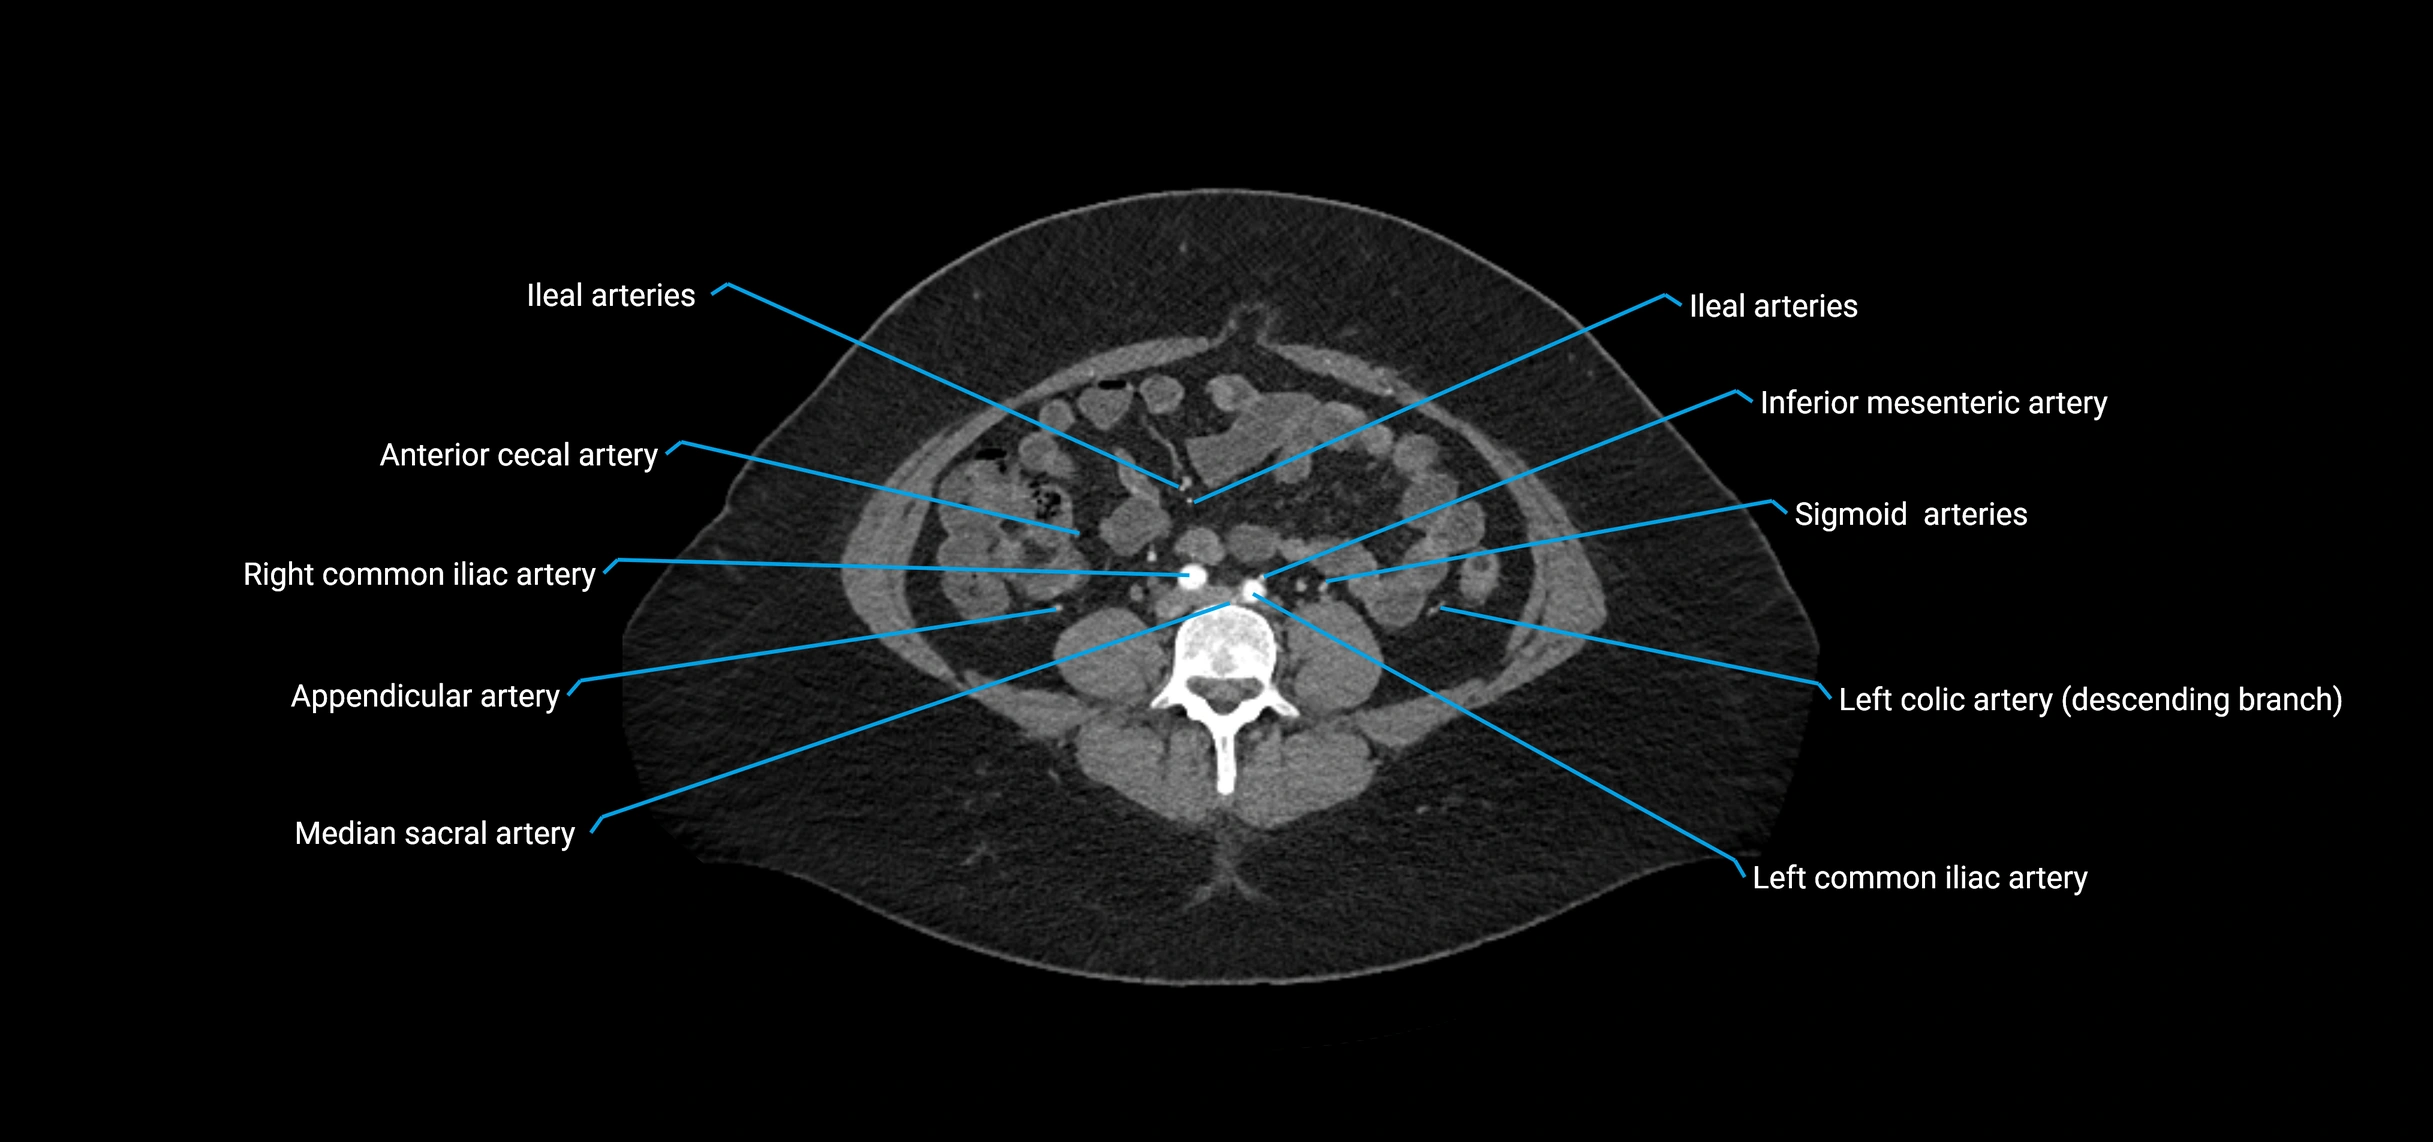

Contrast-enhanced CT (CTA):

• Gold standard for abdominal aortic imaging

• Provides excellent detail of lumen, wall, aneurysm, thrombus, and branch vessels

• Multiplanar and 3D reconstructions help in aneurysm measurement, stent graft planning, and dissection evaluation